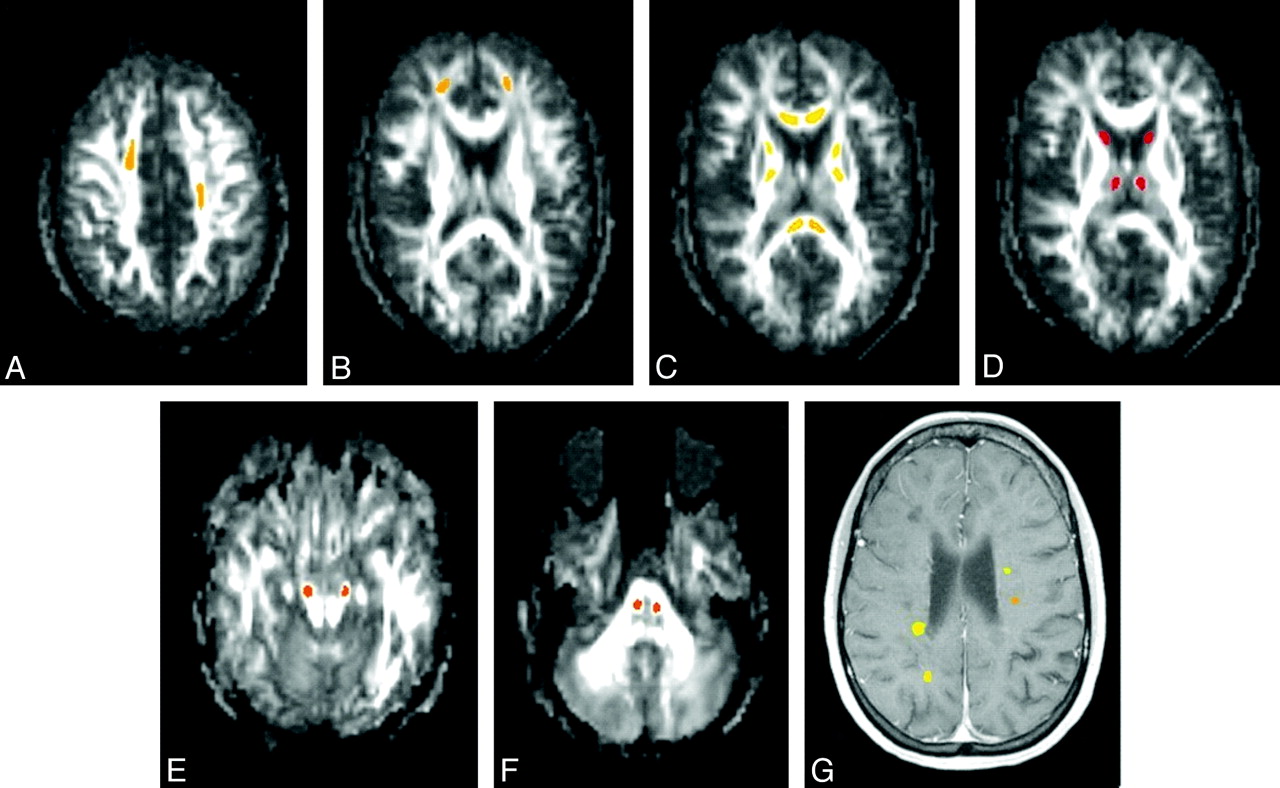

At baseline, all gadolinium-enhancing lesions and 20 regions of interest from NABT (Fig 1) were drawn on each subject by using AFNI.13 For gadolinium-enhancing lesions, regions of interest were drawn over the gadolinium-enhancing region of the lesion on postgadolinium T1-weighted images. For NABT, regions of interest were drawn onto the FA maps to improve the accuracy of longitudinal coregistration. NABT regions of interest were chosen to represent varied white matter and deep gray matter regions. NABT regions of interest were not drawn on areas that showed abnormal signal intensity on either T1-weighted or T2-weighted images at baseline or any follow-up scan. Tissue immediately adjacent to CSF was not included in either gadolinium-enhanced lesions or NABT because of possible later coregistration errors that may include CSF. Regions of interest were followed longitudinally by coregistration of anatomic T1-MPRAGE images acquired at months 1, 2, 6, and 12 to the T1-MPRAGE image acquired at baseline by using Functional MRI of the Brain Software Library.14 Regions of interest were inspected through AFNI at each time point to confirm the accuracy of coregistration and were adjusted when necessary. The reproducibility of these measures in NABT by using this coregistration technique was shown in a previous study, with a median coefficient of variation over 3 annual scans of 9.59% for FA, 2.21% for apparent diffusion coefficient (comparable with MD), 3.70% for λ∥, and 4.19% for λ⊥. Enhancing lesions at baseline were classified at 12 months as either isointense or hypointense (black holes) on T1 images. Isointensity was defined as an inability to visualize any portion of the lesion on nonenhanced T1 images. T1-hole designation at 12 months was then confirmed by a second investigator, and both investigators were blinded to DTI measures. Average values within each region of interest were derived for FA, λ⊥, λ∥, and MD. For descriptive purposes, QBrain Version 1.1.20.0 (Medis Medical Imaging Systems, Leiden, the Netherlands) was used to measure T2 lesion volumes.

Sample regions of interest drawn on a single patient. NABT regions of interest are drawn on FA maps (A−F), and gadolinium-enhancing lesions are drawn on a postgadolinium T1-weighted MPRAGE image (G). The asymmetric placement of regions of interest in A demonstrates a T2 lesion in the right centrum semiovale (T2 images not shown) in which the region of interest had to be shifted anteriorly.